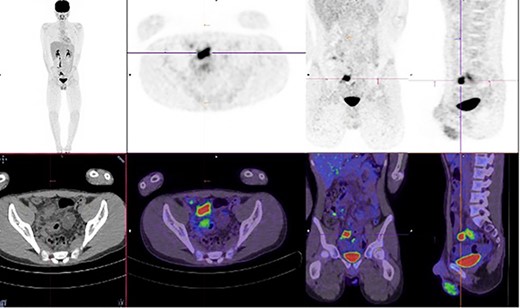

A multi-disciplinary team comprising of surgical, immunology and gastroenterology teams were involved in his care. He was commenced on conservative management with intravenous antibiotics, intravenous immunoglobulin, nil by mouth and total parenteral nutrition for 2 weeks, followed by a slow upgrade in diet for the following 2 weeks. Unfortunately, his pain did not completely resolve, and progress Positron Emission Tomography-CT identified ongoing inflammation in the terminal ileum and further to the rectosigmoid junction (Fig. 2).

Increased metabolic activity in the terminal ileum and anterior to the rectosigmoid junction to the right of midline.